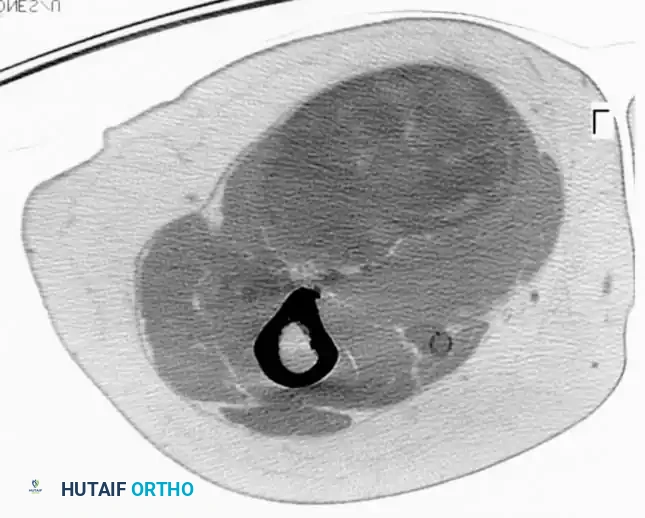

CT scan of the thigh in a 73-year-old patient demonstrating a large pleomorphic liposarcoma adjacent to the sciatic nerve.

Intraoperative photograph demonstrating the wide resection of the pleomorphic liposarcoma, requiring meticulous dissection to preserve the sciatic nerve.

Well-differentiated liposarcomas of the extremities are treated with wide surgical excision alone. Higher-grade variants (myxoid, pleomorphic, dedifferentiated) require multimodal therapy analogous to UPS. Patients with myxoid liposarcoma require specialized staging, including CT of the abdomen and pelvis, and whole-spine MRI due to their unique metastatic patterns.